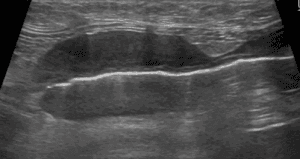

猫の甲状腺腫瘍

甲状腺は、首の気管の両側に位置し、体の代謝を調整する甲状腺ホルモンを分泌する臓器です。猫の甲状腺腫瘍はほとんど良性腫瘍(甲状腺腺腫)ですが、稀に悪性腫瘍(甲状腺癌)も認められます。猫では甲状腺ホルモンを過剰に分泌する機能 […]